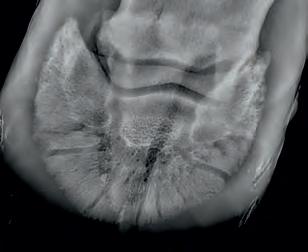

Diagnosis of ulcers in the stomach using a Gastroscope.

Radiographic proof in clinical results

BONE Gold nutritional bone joint and collagen supplement was formulated to provide some of the essential amino acid requirements of collagen type I, II and III (found in bone and connective tissue) in addition to supporting the nitric oxide pathway which has been found to assist in the formation of bone callus postinjury.

Veterinary surgeons have recommended that Bone Gold may assist with sore shins, tendon injuries, ligament injuries, osteoarthritis and post-surgery in horses and polyarthritis, geriatric osteoarthritis, and post-surgery in dogs.

Here is a veterinary radiographic report on a horse with a fracture evident on the medial toe and after treatment and feeding Bone Gold during this period. More information on these products can be found at www.vetgold.com.au

VETERINARY RADIOGRAPHIC REPORT

HORSE: "XXXXXXXX"

DATES OF EXAMINATION: 26TH AUG, 21ST OCT 21 & 17TH NOV '21

PLACE: XXXXXXXXXX FARM

XXXXXXX's left and right front feet were radiographed on 26th Aug, 21st Oct (8 weeks) and again on the 17th Nov '21(12 weeks).

RADIOGRAPHS:

26.08.21: Right Front: Large P3 solar margin fracture evident on medial toe 32.6mm x 4.1mm with approximately 1.4mm separation from parent bone as below left image.

21.10.21: Right Front: Fine residual 4.2mm fracture still evident, approximately 90% resolution

17.11.21: Right Front: Fracture fully resolved

RECOMMENDATIONS:

Radiographic results as of the 17th Nov '21 show total resolution of the original fracture.

XXXXXXX was reshod today utilising off an alloy shoe with a toe clip - inner circumference seated out to avoid any sole pressure.

The horse can return to training. Please do not hesitate to contact me if you have any further queries

COMMENTS:

Solar margin Type IV fractures of this magnitude have well-documented internationally published healing rates of 7 - 12 months. Full resolution of these fractures is rare as most often the fracture fragments are resorbed.

Full resolution in a 3 month period was not anticipated.

The horse was on Bone Gold 3 x scoops fed once per day for this period.

"Go to our webpage or scan the QR Code to see more Bone Gold Radiographic results"